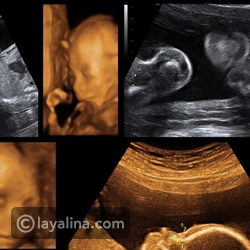

هذا الفيديو يعتمد على تقنية التصوير رباعي الأبعاد 4D ليكشف لنا أسراراً مذهلة عن حياة الجنين داخل رحم الأم.

ويبدو داخل الفيديو كيف يقوم الجنين بتناول الطعام من الحبل السري ثم مضغه بفمه. كما يظهر أيضاً الجنين وهو يبكي ويفرك عينيه، ويعطس.

كما يظهر الطفل أيضاً وهو عابس الوجه بعد إيقاظه من النوم بشكل مفاجئ.